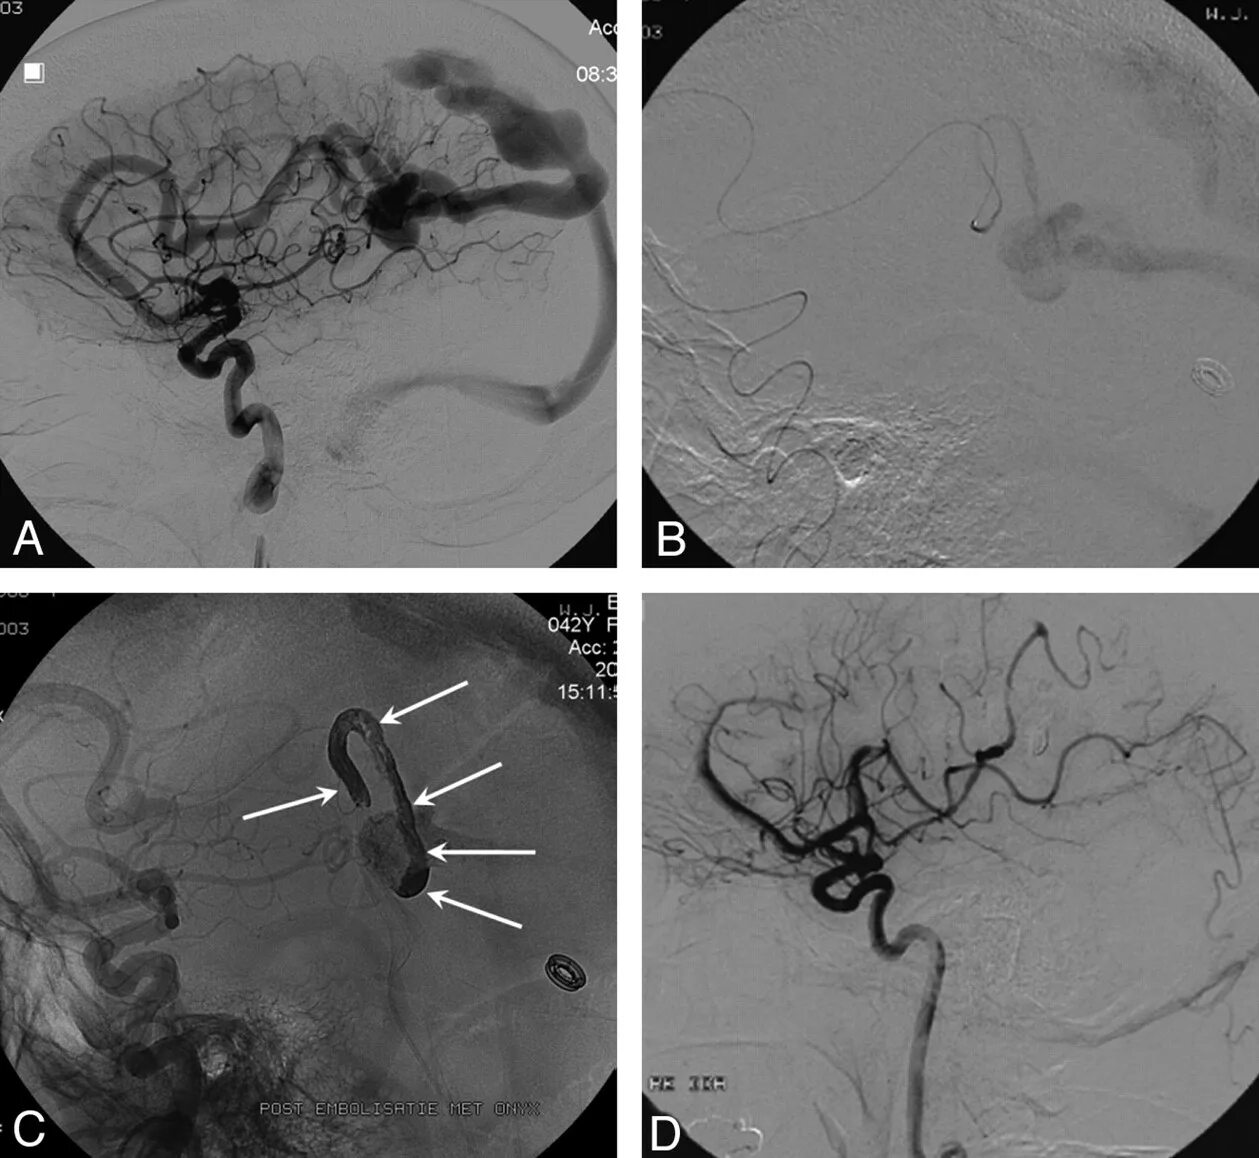

Эмболизация гемангиомы